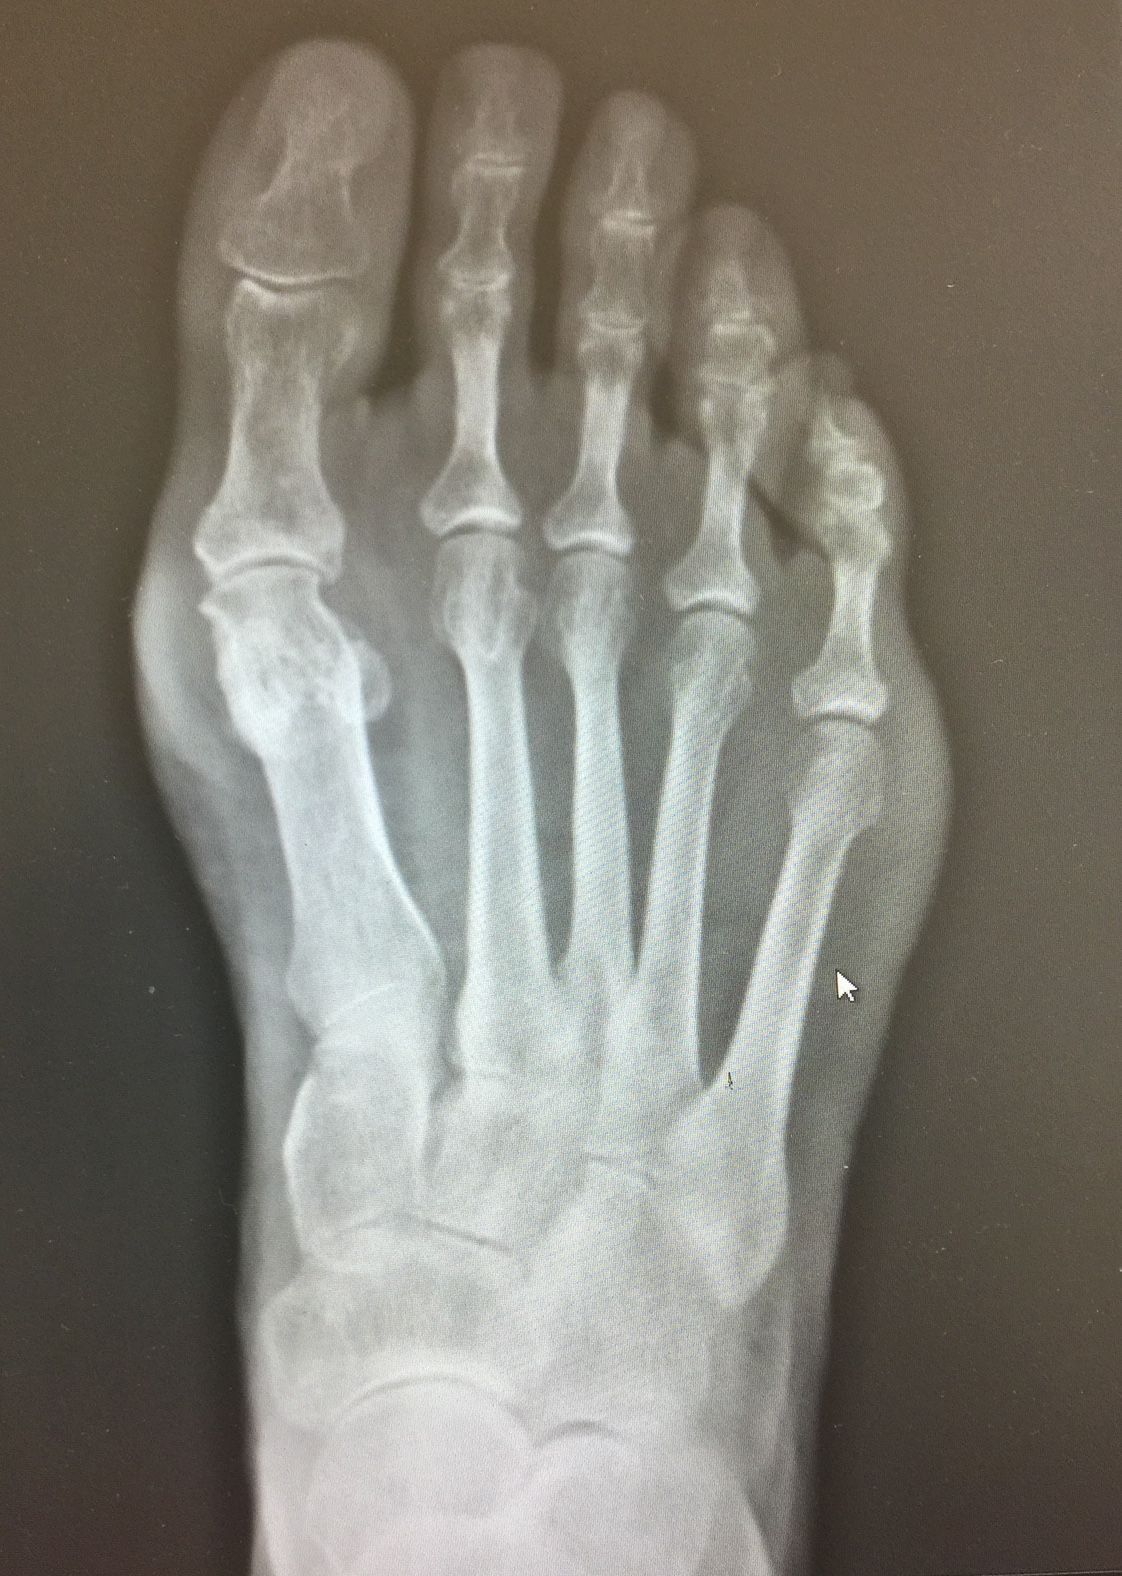

Altro campo del quale mi occupo in modo specifico è la chirurgia mini-invasiva dell'avampiede ( alluce valgo, dito a martello, metatarsalgie). Gli interventi vengono svolti con tagli molto piccoli, senza usare mezzi di sintesi definitivi (viti e camere che rimangono nel piede del paziente), favorendo una ripresa più rapida, con meno dolore per la persona e con un risultato esteticamente migliore.

Foto e video